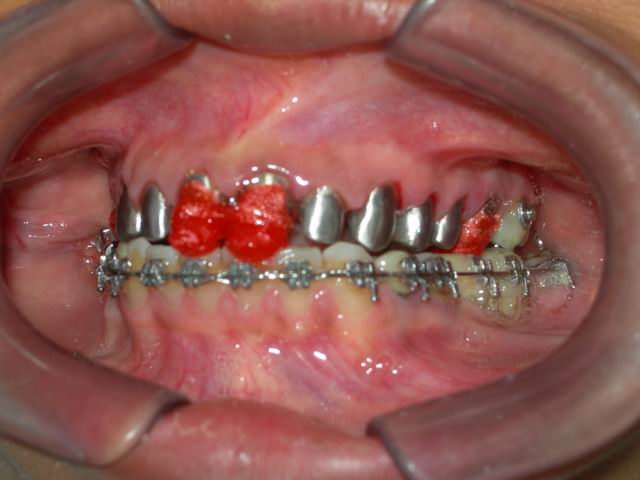

Início da fase reabilitadora, após conclusão do alinhamento e nivelamento ortodôntico: preparo inicial para confecção de núcleos metálicos em dentes naturais desvitalizados (tratados endodonticamente)

Provisórios superiores com dentes de estoque acrílicos após preparos (degastes) protéticos